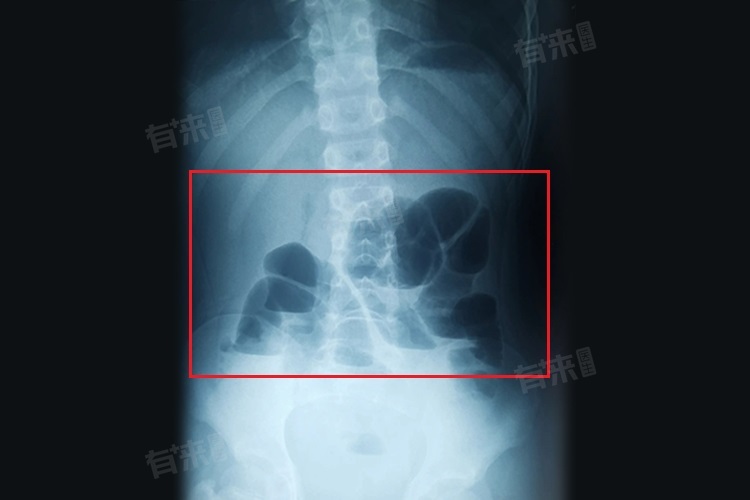

小肠梗阻是指肠内容物通过小肠时受阻,可由肠腔堵塞、肠管受压等方面。若出现腹痛、呕吐、腹胀、停止排气排便等症状,应立即就医。医生会通过腹部X线、CT等检查明确诊断,及时治疗,防止病情恶化。

- 病情监测:密切关注自身症状,如腹痛、腹胀、呕吐、排便排气情况等。若症状加重或出现新症状,如发热、便血等,及时就医。按照医生要求定期复查,进行腹部X线、CT等检查,了解小肠恢复情况。